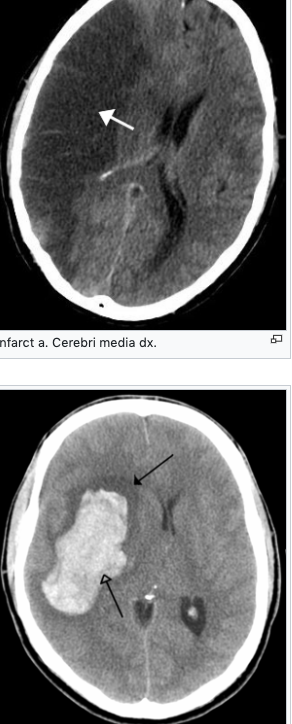

The first 24 hours are typically cared for in the Highly Specialized Stroke Care Center (formerly Stroke Centers, IC) or the Highly Specialized Cerebrovascular Care Center (formerly Complex Cerebrovascular Centers, KCC). Infarct a. Cerebri media dx. Acute typical (hypertensive) basal ganglia bleeding (empty arrow) and surrounding edema (full arrow).

With CMP (due to its severity), timely and correct recognition of the type and stage of the disability is a very important aspect that determines not only the rescue of the patient, but also the subsequent quality of life. The physician and the nursing staff must be able to properly diagnose the patient as soon as possible and begin adequate and effective treatment immediately. The basic examination method is computed tomography (CT) or magnetic nuclear resonance (MRI), which determines what type of CMP it is. An extended diagnostics enabling individualization of the treatment procedure is then multimodal examination in the form of CT-angiography of cerebral arteries and perfusion CT of the brain. The treatment of iCMP versus hCMP is completely different.